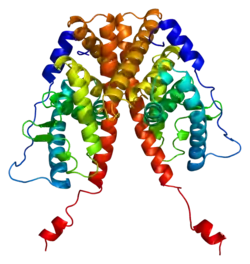

Estrogen receptor alpha (ERα), also known as NR3A1 (nuclear receptor subfamily 3, group A, member 1), is one of two main types of estrogen receptor, a nuclear receptor (mainly found as a chromatin-binding protein[5]) that is activated by the sex hormone estrogen. In humans, ERα is encoded by the gene ESR1 (EStrogen Receptor 1).[6][7][8]

Structure

The estrogen receptor (ER) is a ligand-activated transcription factor composed of several domains important for hormone binding, DNA binding, and activation of transcription.[9] Alternative splicing results in several ESR1 mRNA transcripts, which differ primarily in their 5-prime untranslated regions. The translated receptors show less variability.[10][11]